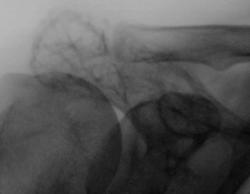

Акромион лопаки имеет ячеестое строение, несколько вздут. Я бы подумао об ОБК. А гистология уже есть?

ДА,мы тоже подумали об ОБК,при пункции-цит картина ОБК.А после операции гистология гистиоцитомы. Во какая штука.

Была сцинтиграфия скелета,накопление только в этом месте.Симметричный сустав на изменен.

Вот собственно и вся история.Кстати и жалоб- не было.А про размер своего надплечья пациент думал,что так и надо,рука-то правая .

На мой взгляд, изменения есть и в клювовидном отростке, частично в шейке лопатки, да и акромиальный отдел ключицы, частично, задействован?

Все врено,Валентин Львович.